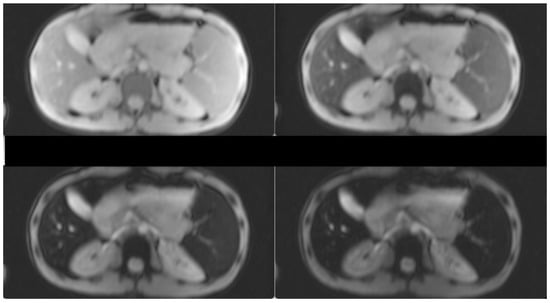

3. Case Presentation